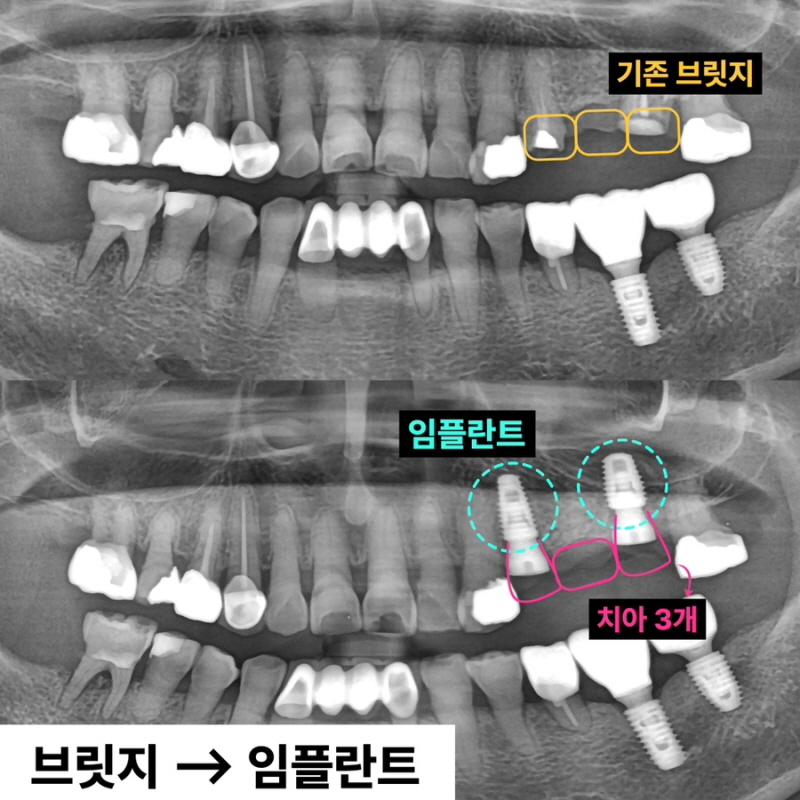

안녕하세요 덴탈킹 박상준입니다. 오늘은 브릿지를 제거하고 동시에 상악동 수술 그리고 임플란트까지 진행했던 케이스를 보여드리겠습니다.

"기존 브릿지가 흔들리고 깨졌어요" 60대 여자 환자분이었습니다. 기존 브릿지를 다시 살릴 수 있는지 확인합니다.

이미 신경치료된 치아 뿌리 끝에 염증이 잡혀있고 브릿지 아래로 2차충치가 크게 생겨서 임플란트로 치료 계획을 정했습니다. 임플란트 2개를 심고 치아 머리(크라운) 3개를 만듭니다. 여러 개의 임플란트를 심을 때 꼭 개수대로 임플란트를 심을 필요는 없습니다. 과거에는 발치, 상악동 수술, 임플란트를 전부 기다리며 나눠서 진행했는데 시간이 너무 오래 걸립니다. 저는 최대한 치아가 없는 기간을 단축시키기 위해서 치아를 뽑고(발치) 동시에 임플란트를 심으며 뼈가 없는 경우 상악동 수술을 동시에 진행합니다.

발치, 상악동 거상, 임플란트 식립 모두 이상적인 모습입니다. 과거 임플란트가 없던 시절에는 브릿지 치료가 일반적이었습니다. 하지만 현재는 치아가 없을 때 양 옆의 치아를 갈아서 씌우는 치료는 임플란트 등장으로 없어지고 있습니다. 또한 오래된 브릿지가 흔들리거나 잇몸에 염증이 생긴다면 임플란트로 교체가 필요할 수 있습니다.